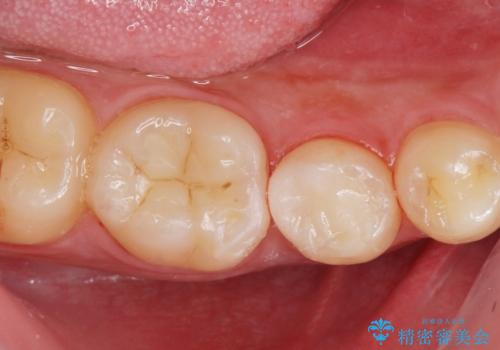

歯と歯の間に虫歯(コンタクトカリエス)がありましたので、拡大鏡下で虫歯を取り、白い詰め物(e-maxインレー)で治療を行いました。

適合の良い詰め物が入りました。

歯と歯の間は歯ブラシだと磨くことができないので毎日歯間ブラシやフロスを使うことをお勧めします。